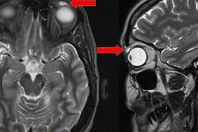

بعد ضياع 28 عامًا.. استخراج عدسة لاصقة من جفن امرأة